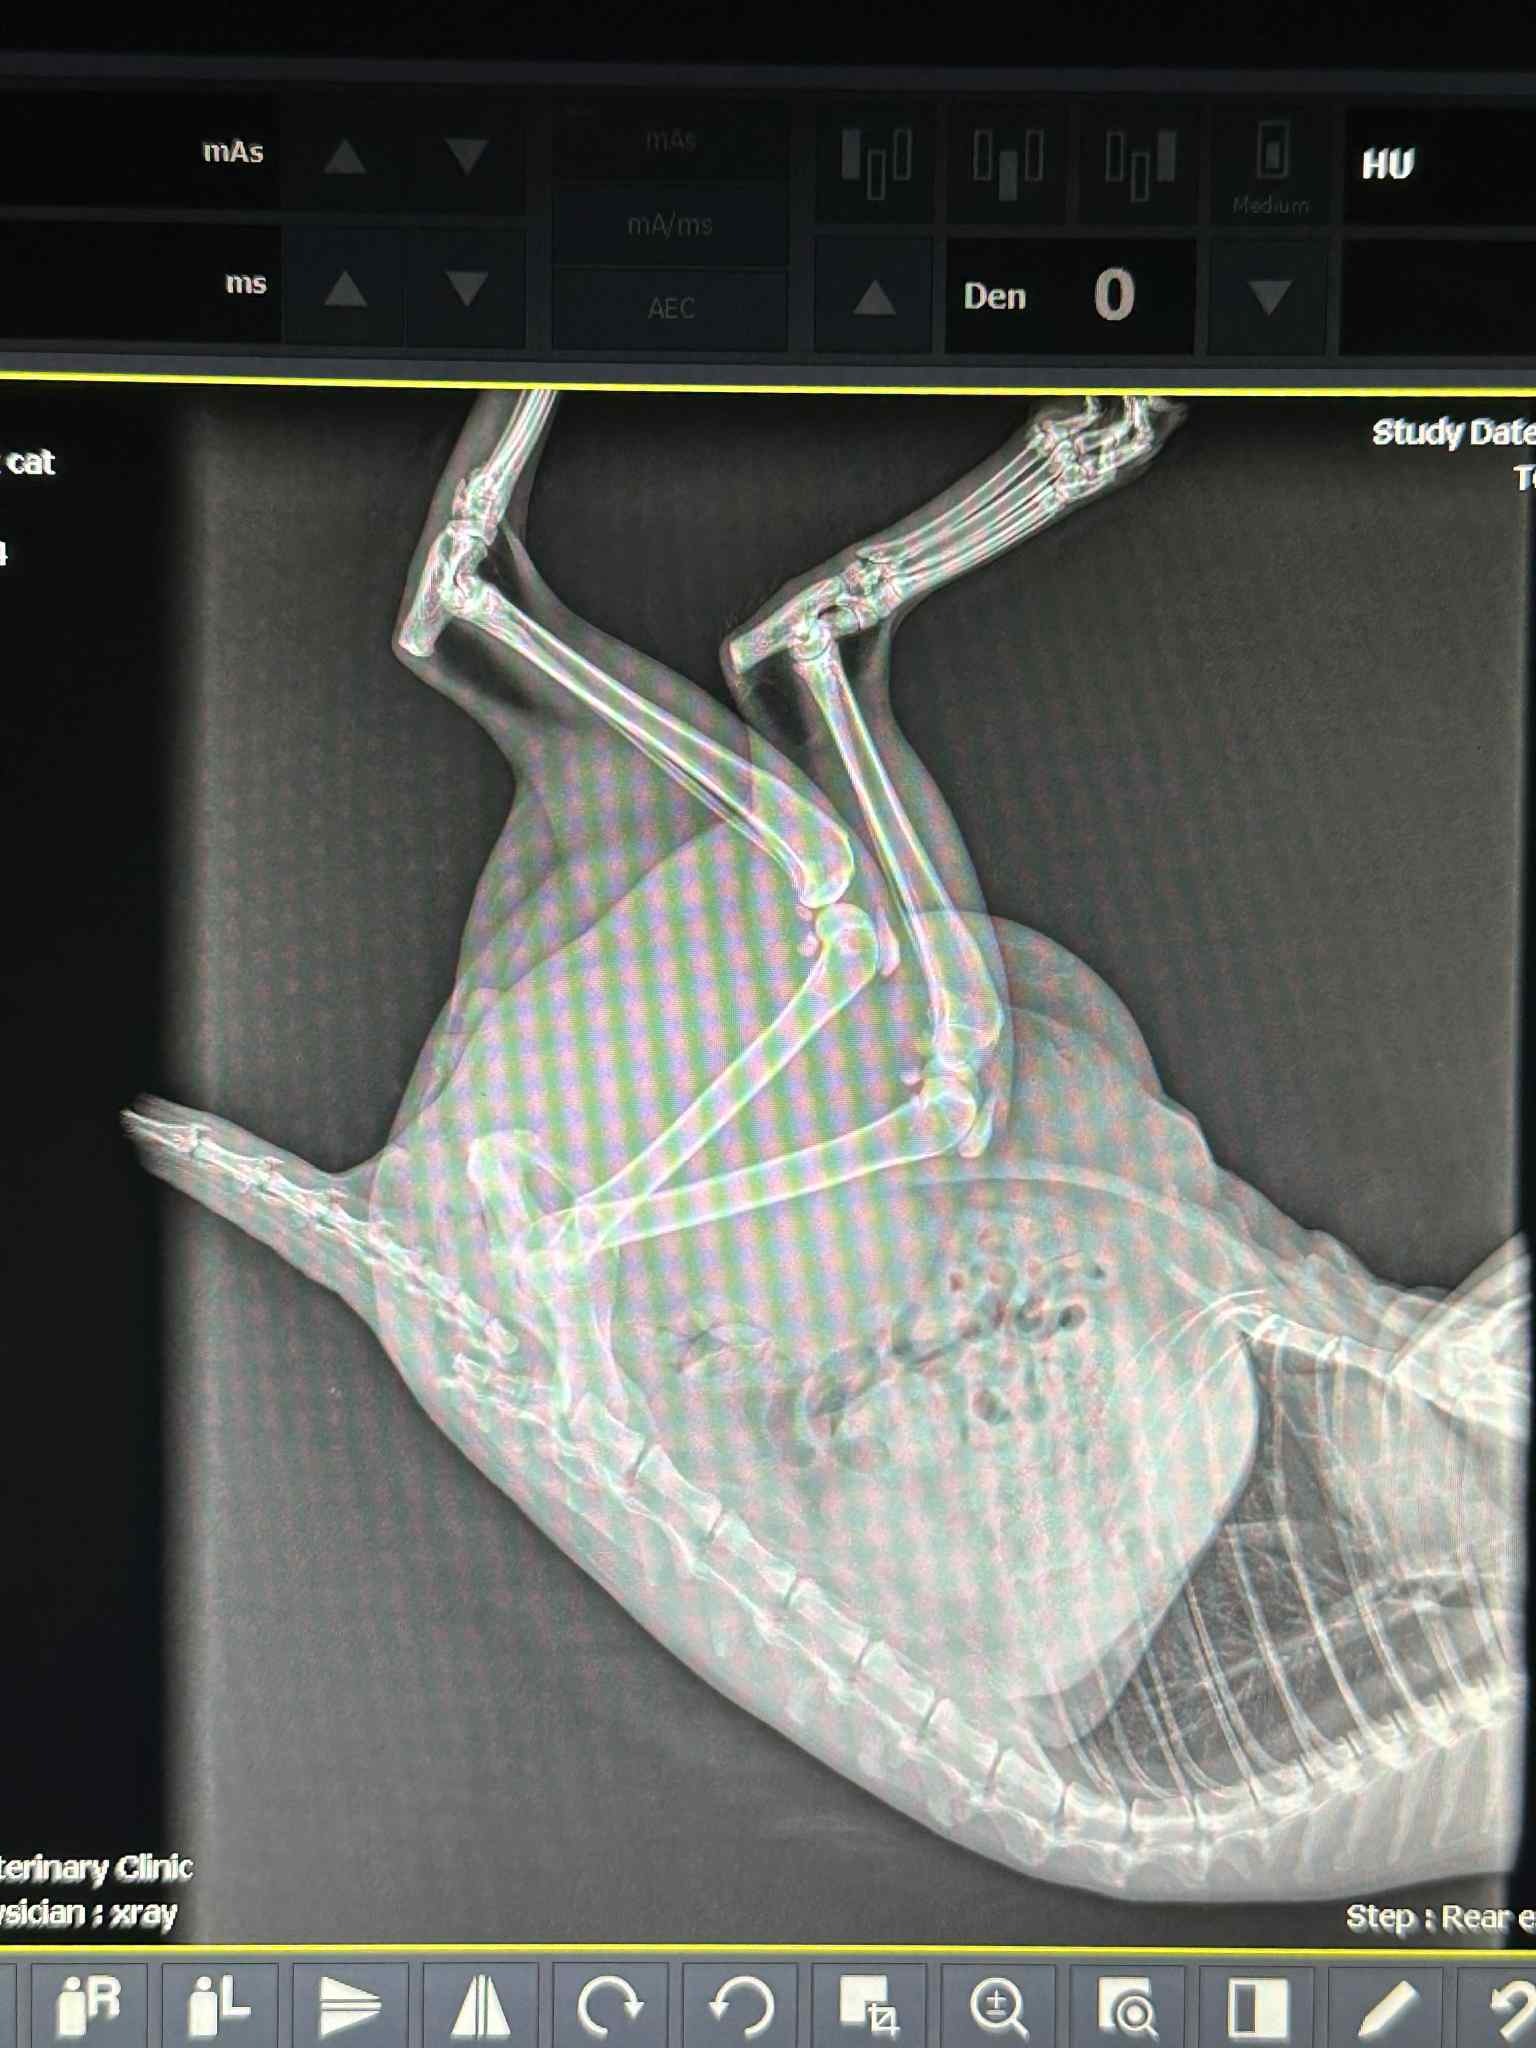

We were able to get a hold of Destinee Nugent, a Licensed Wildlife Rehabilitator, who rushed over immediately. She was able to get Milo into a safe place for the night and got him x-rays the following day. It appears as though he has a broken tail and a broken pelvis. He will be seeing the veterinarian on July 31 for a more thorough check.